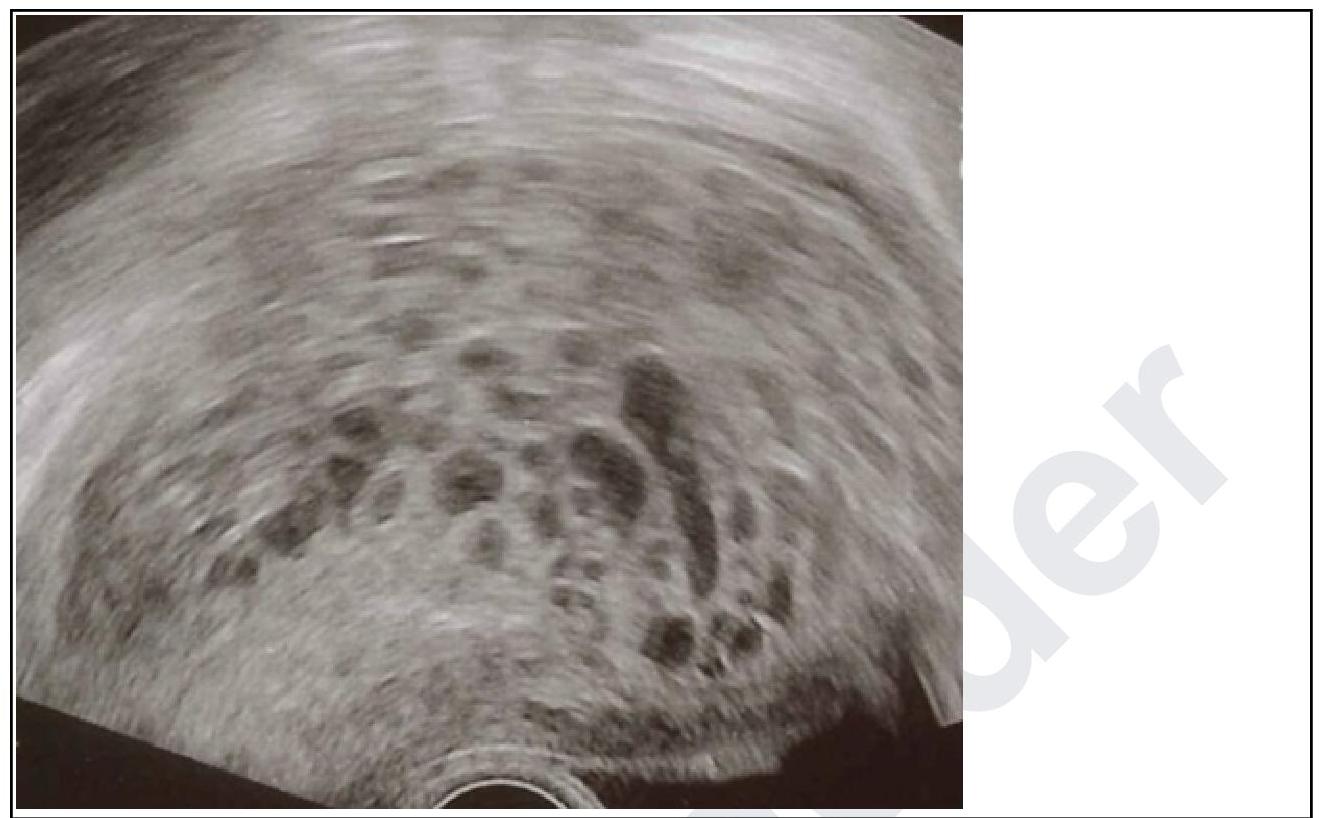

A primigravida in her 10th week of gestation presents with spotting. On examination, the uterus corresponds to 12 weeks. Transvaginal ultrasound was done and it is given below. What is your diagnosis?

Explanation: ***Hydatidiform mole*** - The ultrasound image shows a **"snowstorm" appearance**, characterized by multiple echogenic vesicles or cystic spaces within the uterine cavity, which is pathognomonic for a hydatidiform mole. - The clinical presentation of **vaginal spotting**, a uterus size **larger than expected for gestational age** (12 weeks uterus size at 10 weeks gestation), and possibly elevated hCG levels (though not given here) are all highly suggestive of a molar pregnancy. *Blighted ovum* - A blighted ovum, also known as an anembryonic pregnancy, involves a **gestational sac without an embryo**. - The ultrasound typically shows an empty gestational sac and does not feature the characteristic "snowstorm" pattern of a hydatidiform mole. *Ectopic pregnancy* - An ectopic pregnancy occurs when the **fertilized egg implants outside the uterus**, most commonly in the fallopian tube. - The ultrasound would typically show an **empty uterus** and a gestation outside the uterine cavity, usually with a mass in the adnexa, which is not seen here. *Missed abortion* - A missed abortion is characterized by the **death of the embryo or fetus but retention** within the uterus. - Ultrasound would show a **fetus without cardiac activity** or a gestational sac that is smaller than expected, without the typical vesicular pattern of a mole.